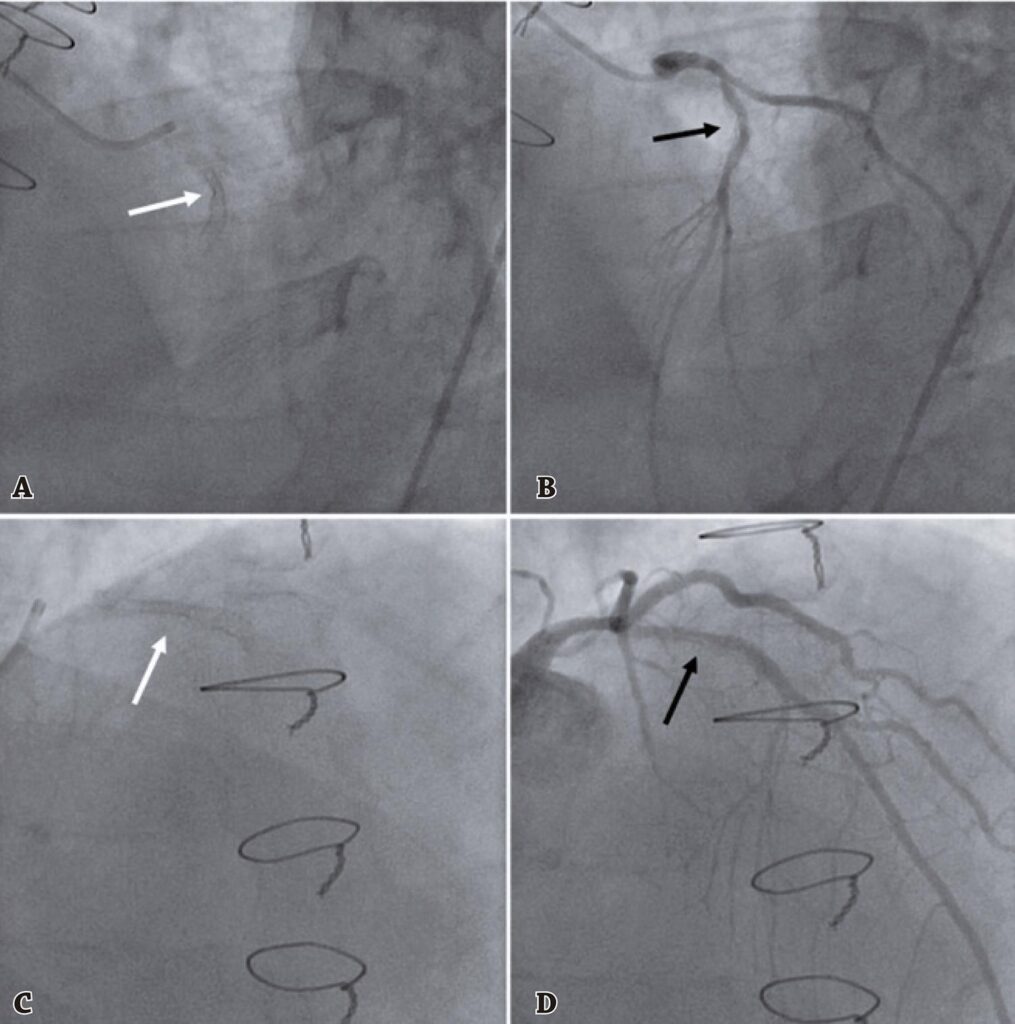

A aterectomia coronária com Excimer Laser melhorou significativamente nos últimos anos, utilizando emissão ultravioleta de alta energia e comprimento de onda curto, com menor penetração e menor emissão de calor, resultando em menos danos aos tecidos e menos complicações. Descrevemos o caso de um paciente do sexo masculino, 66 anos, ex-tabagista, hipertenso, diabético, dislipidêmico. Foi submetido a múltiplas intervenções coronárias percutâneas na artéria descendente anterior com stents não farmacológicos e farmacológicos. Na última intervenção coronária percutânea, o stent foi subexpandido, e o paciente apresentou trombose aguda do stent e reestenose recorrente do stent. Foram realizadas novas intervenções coronárias percutâneas com aterectomia coronária com Excimer Laser adjuvante, devido à angina refratária, com uso de carga progressiva e injeção de soro fisiológico, seguidas de posterior insuflação de balão de alta pressão e implante de stent farmacológico, com resultado excelente. No acompanhamento de 8 meses, o paciente se manteve assintomático.